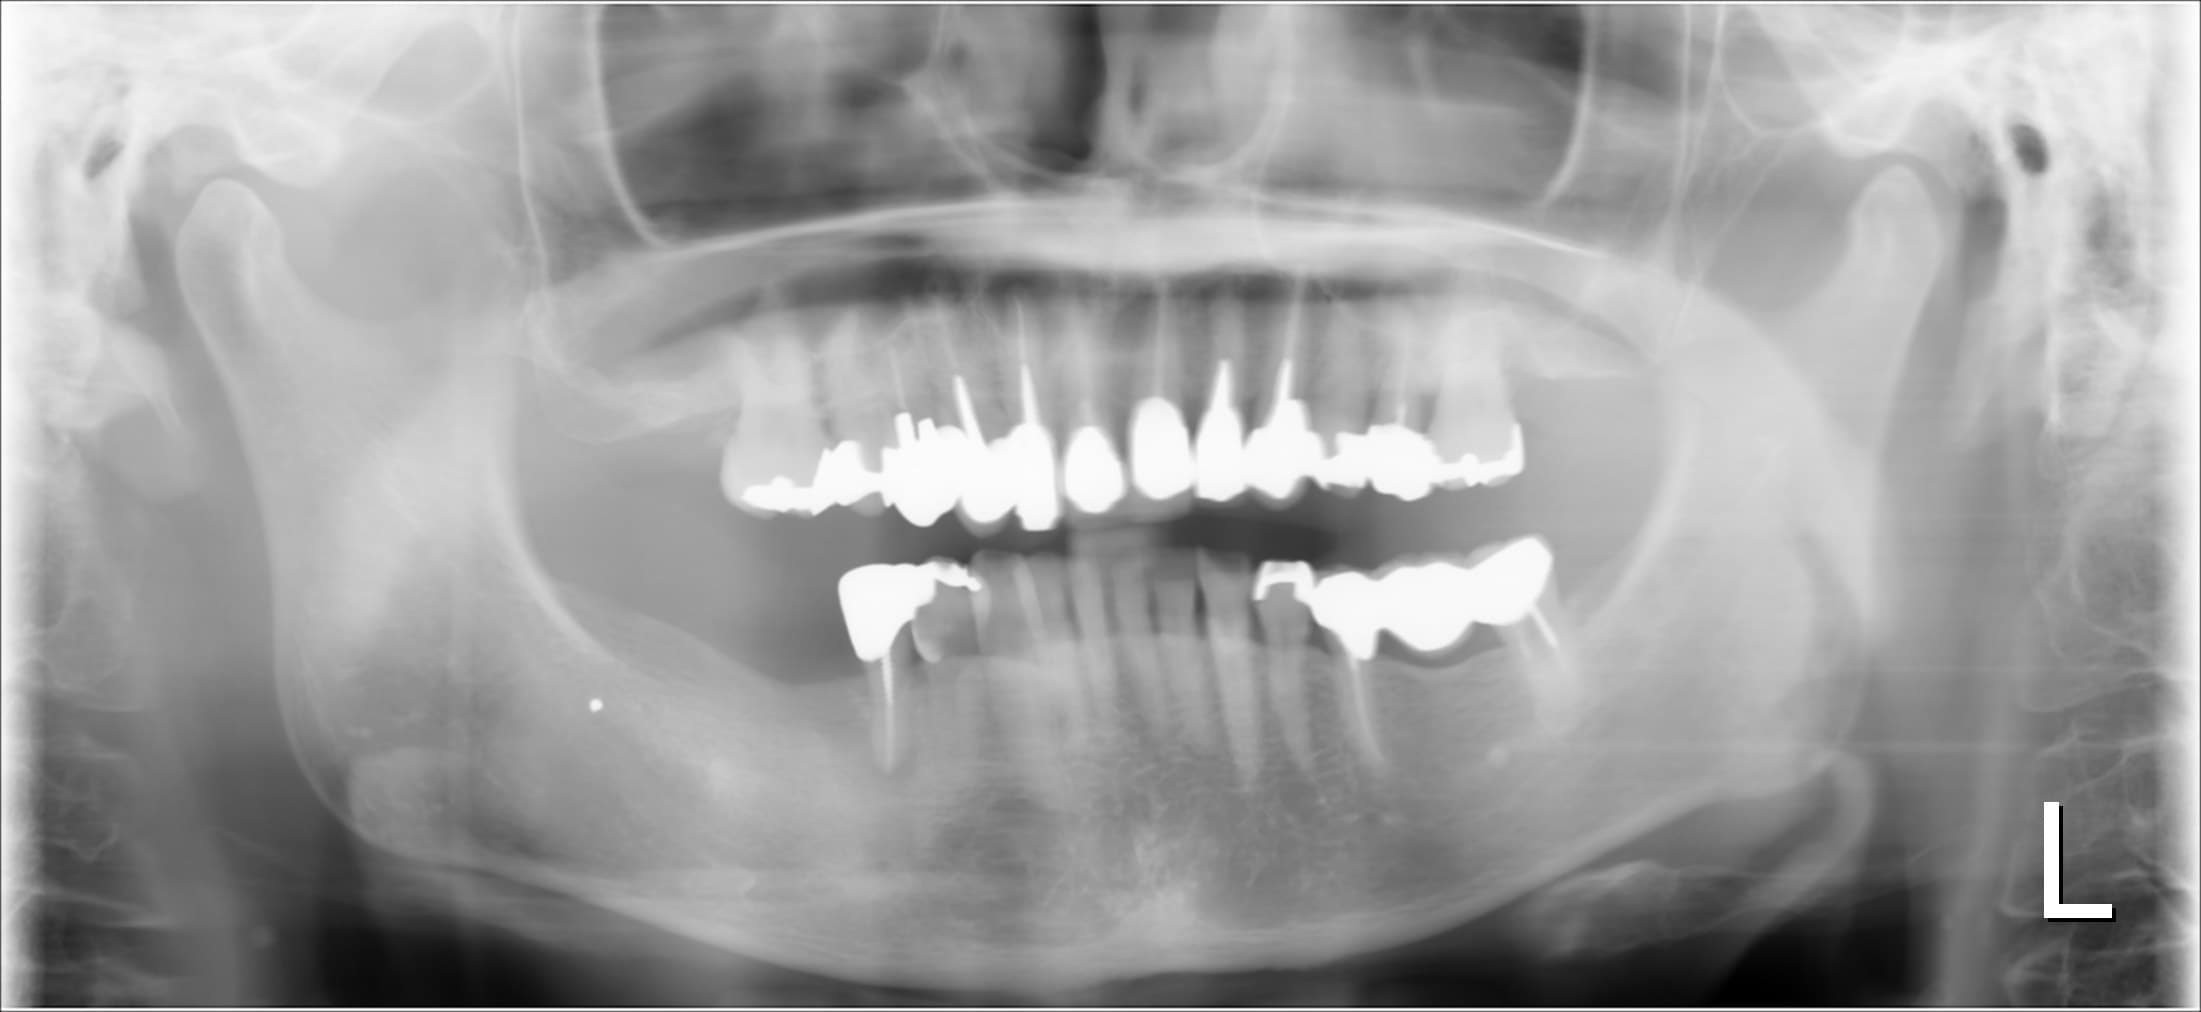

どうにかしたいけど、痛いのはイヤ・・・

こんにちは。 南館歯科クリニックの歯科衛生士の山崎です。 今回ご紹介する症例は、70代女性の方です。 実は以前、歯周治療を他院で行い、その後、上の前歯にきれいな被せ物が装着してありました…

せっかくやるなら、しっかり治したい

こんにちは。南館歯科クリニックの歯科衛生士の山崎です。 今回ご紹介する歯周専門治療のケースは、30代男性の方です。 小学生のお子さんから口臭を指摘されたり、ご自身でも歯肉が下がって歯周病…